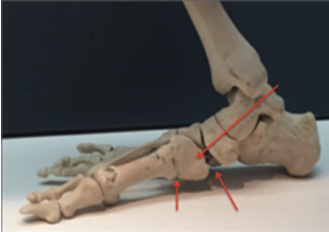

Arthroereisis

When the foot rolls in this gap reduces in size and expands when the foot rolls out. By placing the right size implant in the sinus tarsi, we can limit the amount of rolling in (pronation) of the foot.

This implant is not always tolerated by the patient and in some cases, it has to be removed. It is unlikely that an arthroereisis would be used in isolation. NICE guidelines in 2009 recommended caution with regard to the use of this device as the long-term data on its efficacy and potential complications was not known.